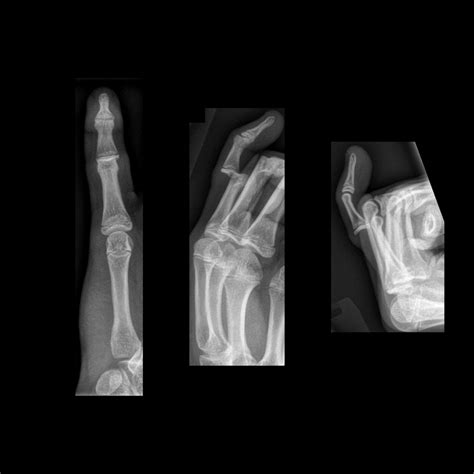

• Intra-articular Fractures: These breaks extend into the distal interphalangeal (DIP) joint, which can be more complex and potentially lead to long-term stiffness if not managed correctly.

When you visit a healthcare professional, the diagnostic process is usually straightforward. The physician will perform a physical examination to check for stability and nerve function. To confirm the diagnosis of a distal phalanx fracture, the doctor will order an X-ray. Radiographic imaging is crucial because it allows the medical team to see the exact location and pattern of the break.

X-ray Imaging Confirms the fracture site and determines if surgery is needed.